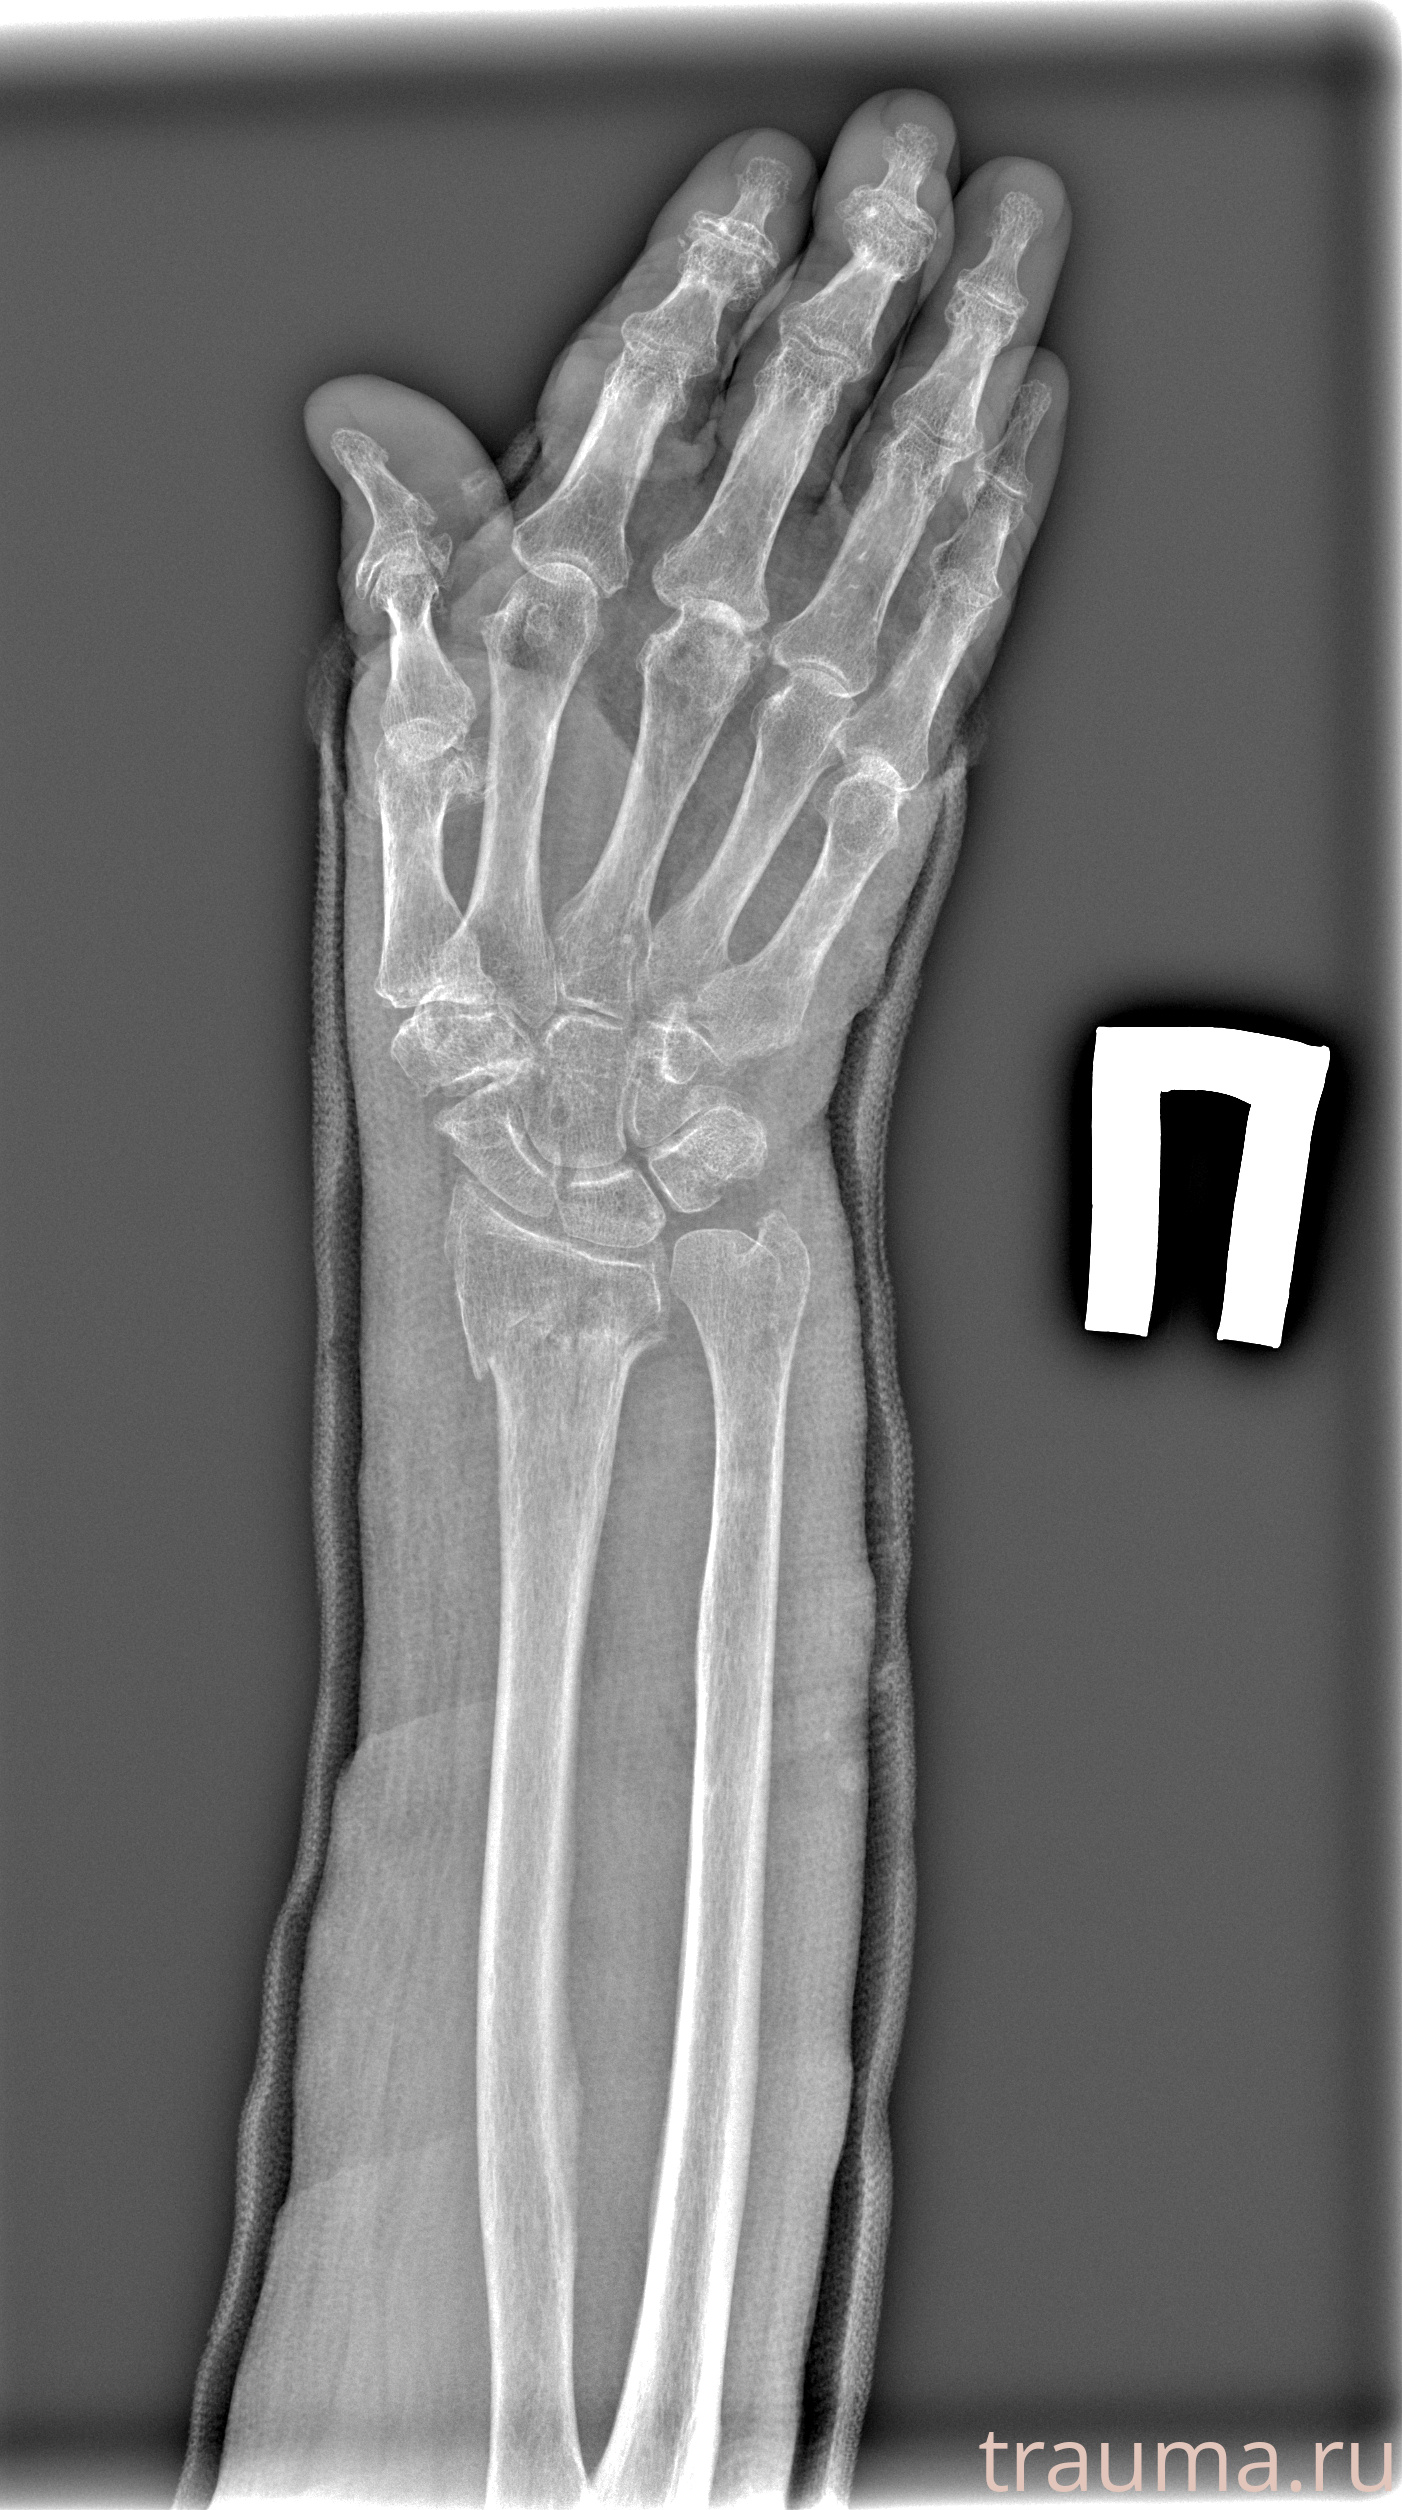

Рентген на дому: по вашему адресу приезжает врач-рентгенолог, травматолог-ортопед с мобильным рентгеновским аппаратом, проводит диагностику травмы или заболевания, делает необходимые рентгенограммы, дает рекомендации по дальнейшему лечению. Получить качественные снимки в домашних условиях возможно благодаря уникальной методике, разработанной МосРентген Центром для института  Склифосовского